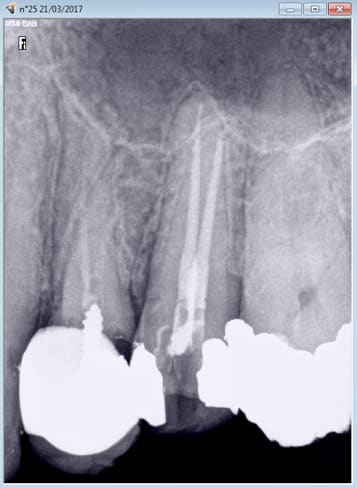

Mais je m'améliore , celle de 14 h. Nouveau patient ( mais est utile de le préciser quand on voit l'endo de 24, encore un problème technique hein ? ) ) Pulpite 25 ( signe d'appel status lol !) endo. Il va y avoir la 12 à reprendre non ? -)

Capture d écran 2017 03 21 22.36 - Eugenol

Capture d écran 2017 03 21 22.37 - Eugenol